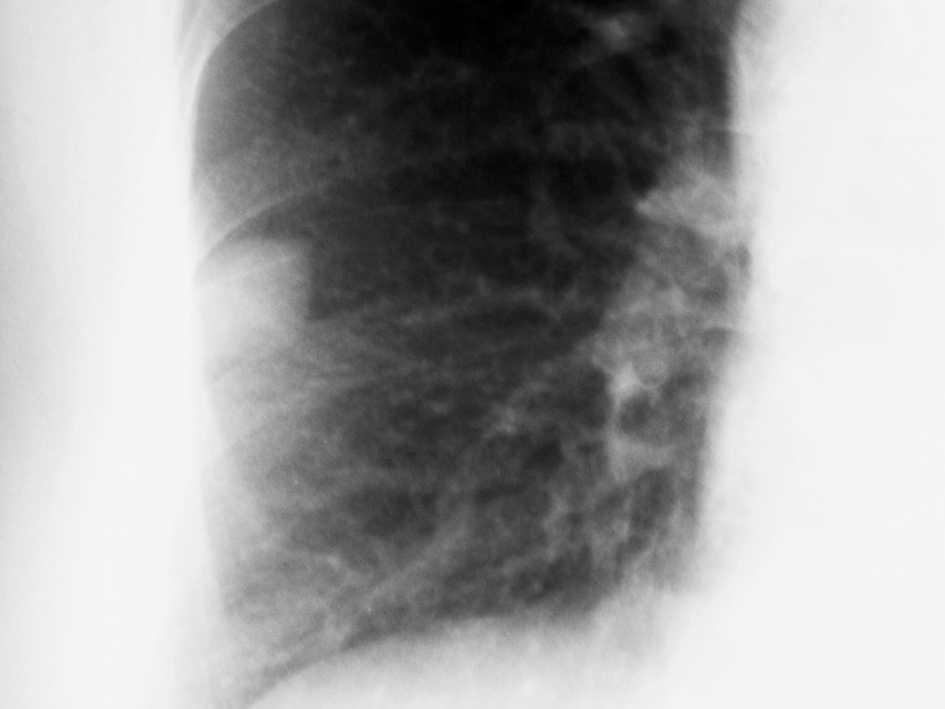

En las pruebas complementarias la analítica (bioquímica, hemograma y coagulación) es normal. Electrocardiograma muestra ritmo sinusal. En la radiografía de tórax (figs. 1 y 2) se aprecia una imagen nodular de 2-2,5 cm localizada en el lóbulo medio derecho (LMD). Con el diagnóstico de bronquitis se cita en la consulta de neumología a la paciente para estudiar la imagen nodular pulmonar de forma preferente, instaurándose un tratamiento broncodilatador y antibiótico.

Figura 1. Radiografía de tórax.